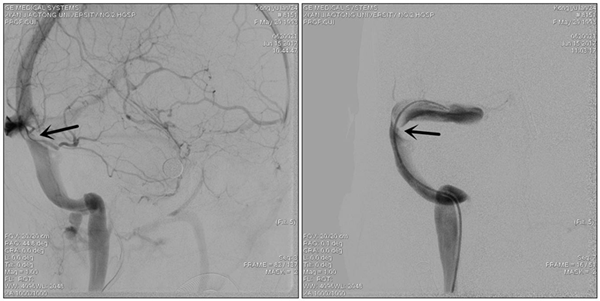

患者转入我科时头痛剧烈、烦躁不安、双眼视力仅有眼前指数,强力脱水的状态下颅内压仍大于600mmH2O。我们按压了分流阀,发现分流阀已经堵塞,家属急切的要求我们重新给她做分流手术,缓解颅内压。但崔刚、许刚二位医生仔细了解患者病史,认真研究患者的影响资料,考虑患者颅内高压、视力下降、癫痫发作这一系列症状是由于颅内静脉窦狭窄造成的,要想彻底解决这些问题的关键不是分流手术,而是恢复颅内静脉窦的正常回流。经与患者家属的充分沟通后,家属接受了我们的诊疗思路,次日为患者行全脑血管造影术,发现患者右侧横窦狭窄严重,经测量狭窄远近端压力差为310 mmH2O。根据国际指南,狭窄远近端压力差大于130 mmH2O就有实施静脉窦支架成形术的指征。为了进一步确定手术效果,崔刚、许刚二位医师先为患者实施了静脉窦狭窄球囊扩张术,球囊扩张后,患者诉头痛明显缓解、视力也开始恢复。次日腰穿显示颅内压已经降到了270mmH2O,患者及家属非常满意。

图片1_副本.png

术前造影显示静脉窦狭窄